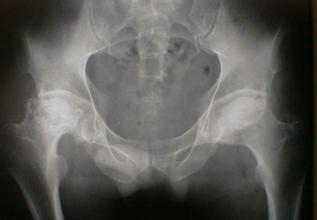

股骨头坏死了要怎么护理身体?如果生活习惯不好,如经常饮酒、剧烈运动等等,都可能引起许多的疾病,如股骨头坏死等。股骨头坏死会引起髋关节疼痛、活动受限等,会给患者朋友带来很大的影响。因此股骨头坏死后,要积极做好护理身体的工作。 》》》百看不如一问,点击此处云骨专家在线为你解答疑惑

股骨头坏死了要怎么护理身体?